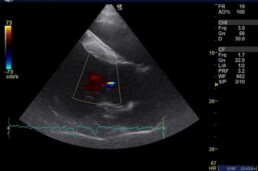

Herz-Klappen-Insuffizienzen (ungenügender Schluss der Herzklappe):

- mittelgradige Aortenklappeninsuffizienz

- mittelgradige Mitralklappeninsuffizienz

- geringgradige Trikuspidalklappeninsuffizienz

In Ruhe verursacht dauerhaftes Vorhofflimmern, an das der Körper sich einigermaßen adaptiert hat, meist keine Störung der Kreislauffunktion, da hier die Vorhofkontraktion nur einen geringen Beitrag zur Kammerfüllung leistet. Tritt es jedoch, wie bei diesem Wallach, unvermittelt auf, und wohlmöglich noch unter Belastung kann es zur Synkope führen. Bei dem vorgestellten Pferd liegen zusätzlich deutliche Rückflüsse an drei Herzklappen, sowie eine geringgradige Dimensionsveränderung (Herzvergrößerung) infolge einer Volumenüberlastung vor, was die Symptomatik verschlimmert.